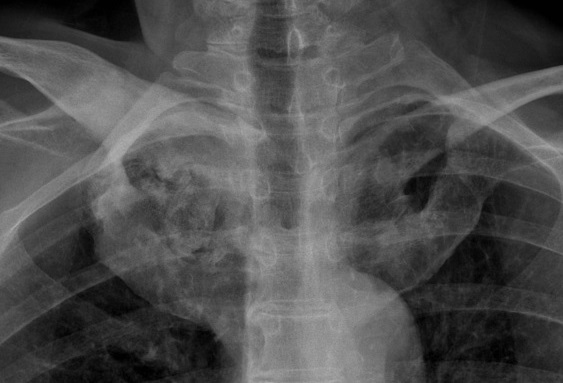

Image radiologique PA

d'une fibrose pulmonaire avec aspect de fibrose de

articulaire sterno-claviculaire gauche d'une

spondilite ankylosant |

Aspect de fibrose , calcifiee du ligament

inter-epineuse posterieure et ligament para

vertebrale de L1-L5 en formation image de colonne de

bamboo ( bamboo spine ) |